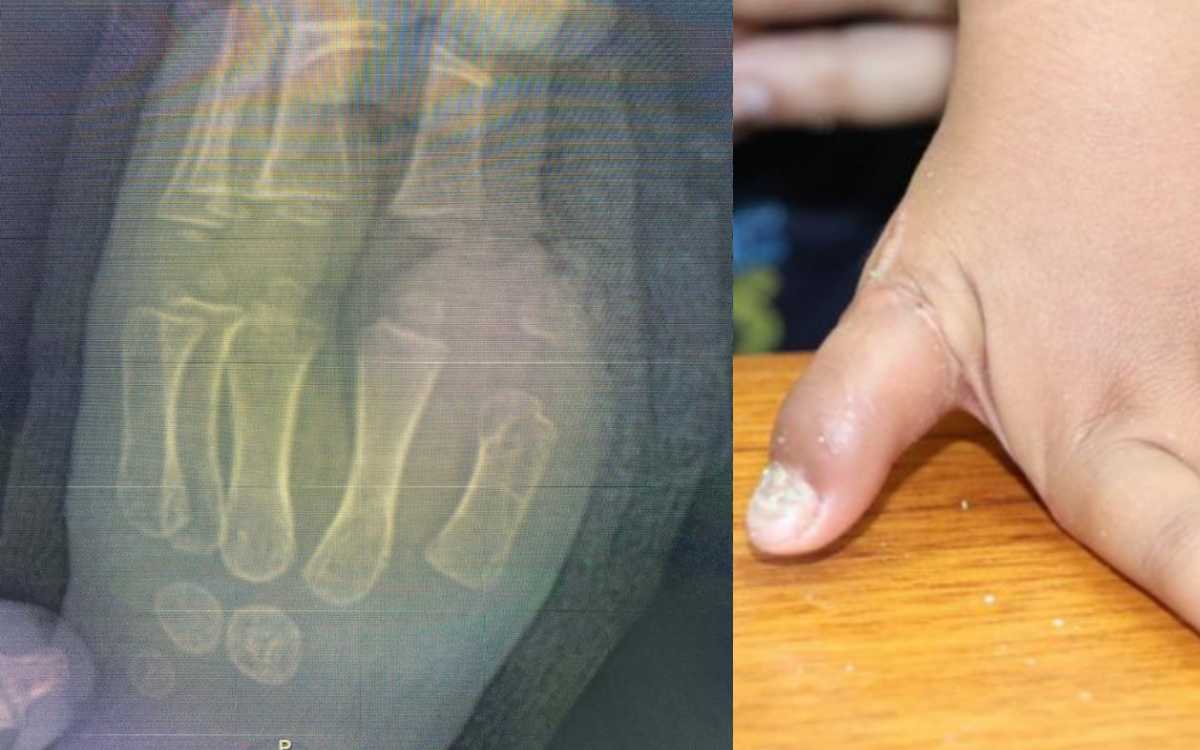

Cirujanos plásticos del IMSS reimplantan dedo pulgar a niño de 1 año tras sufrir accidente

Cirujanos del Instituto Mexicano del Seguro Social (IMSS) en Nuevo León, reimplantaron con éxito un dedo pulgar a un niño de 1 año 8 meses, después de que un abanico metálico le arrancó la extremidad. Se espera que recupere y desarrolle la funcionalidad de su mano izquierda casi al 100 por ciento. La unidad médica…